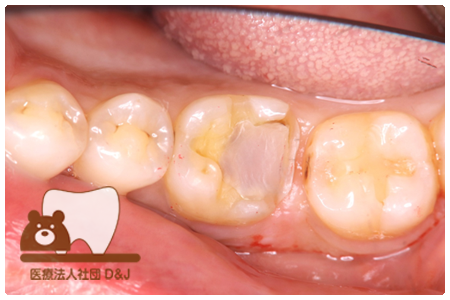

症例3フリジルコニアクラウン 左上6

治療前

治療後

59歳 男性

- 治療内容

- 虫歯で大きく失われた歯に対して、土台としてファイバーコアを使用し、その上にフルジルコニア製の被せ物を装着しました。見た目と強度を両立した自由診療の治療です。

- 治療期間

- 根の治療含めて3カ月半

- 費用

- 自費

フリジルコニアクラウン:77,000円(税込)

(R8.2月時点)

- その他の治療の費用は含まれておりません。

- リスク・副作用

- 強い力が加わると割れる可能性があります。また、噛み合わせや歯ぎしりの影響で脱離することがあります。